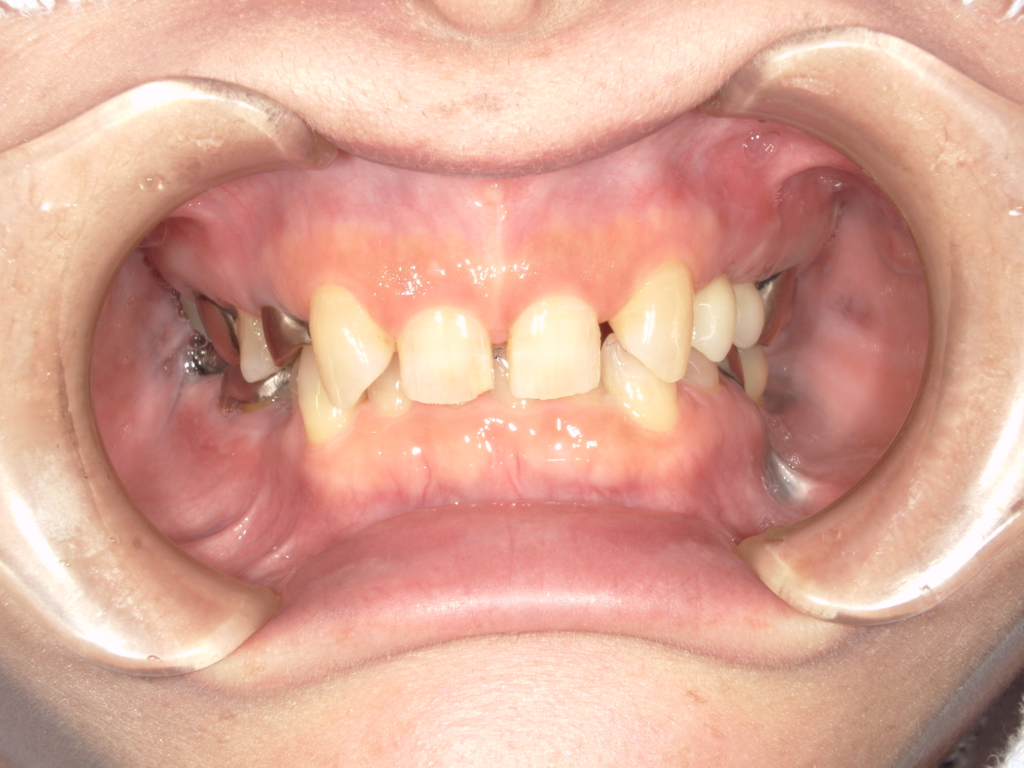

N様 50代 男性 インプラント実例 #37

前歯の4本が、残すのが難しい状況となり、インプラント治療を行いました。

インプラントは前歯に2本埋入し、4本の前歯を作っています。歯を抜くと同時にインプラントを埋入し、仮歯を作りました。その後2ヶ月で、被せ物を入れました。被せ物は、セラミックスで作っています。

治療前

治療後